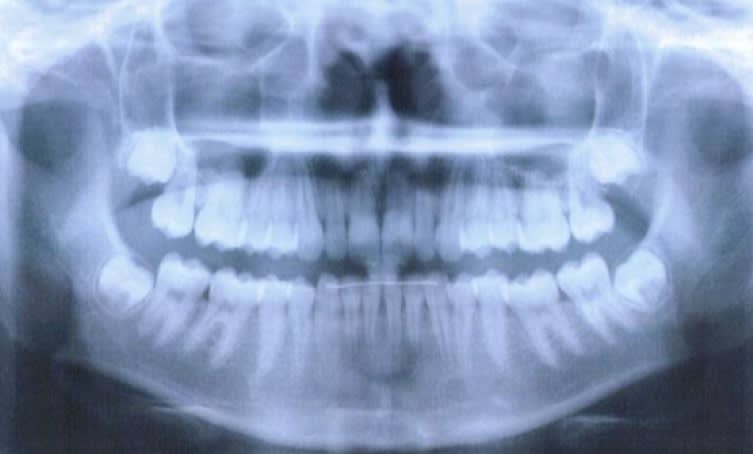

Pour répondre à ta question : il faut poser l'indication. Quand les germes sont encore dans la branche à 16 ans (comme sur ta pano), il y a de forte chance qu'il n'y ait pas de place... Pour les autres on surveille.